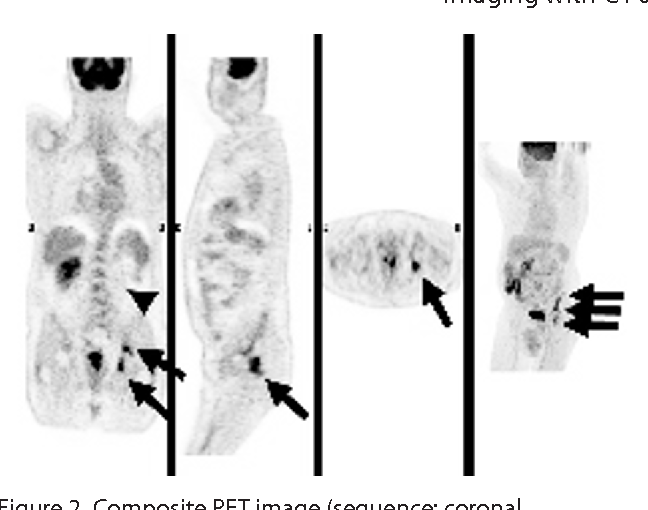

![[89Zr]Zr-girentuximab for PET–CT imaging of clear-cell renal cell ...](https://www.thelancet.com/cms/10.1016/S1470-2045(24)00402-9/asset/700721d8-bd15-46c0-a967-f0daeac9b4ac/main.assets/gr2b_lrg.jpg)